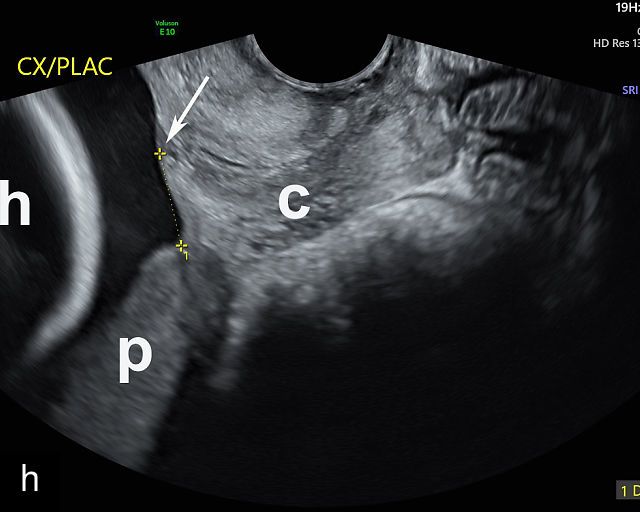

5

Placenta previa and low-lying placenta. (a) Transabdominal grayscale ultrasound image suspicious for placenta previa. The placenta (PL) appears to overlie the internal cervical os (CX). Note the time stamp: 2:19:37. (b) Transvaginal ultrasound of the same patient taken approximately 50 minutes later. Note the time stamp: 3:10:25. The internal os and the lower placental edge are both clearly seen, and the placenta does not overlie the internal os. Because the lower placental edge is 1.93 cm from the internal os, it will likely resolve by the third trimester. (c) Transabdominal grayscale ultrasound of placenta previa. The placenta (p) covers the cervix, but the cervix, especially the internal os, cannot be visualized due to shadowing. (d) Transabdominal grayscale ultrasound of placenta previa. The placenta (p) covers the cervix (c) but shadowing obscures adequate visualization. The internal os is indicated by the arrow. (e) False-positive image of placenta previa on transabdominal grayscale ultrasound. The bladder (b) is full, pushing the anterior and posterior walls of the lower uterine segment (ls) together making it appear that the placenta (p) overlies the internal os of the cervix. In reality, the line depicted by the arrowheads is where the anterior and posterior walls of the lower segment are in proximity to each other. The cervix is much lower and is obscured by shadowing (c). (f) Transabdominal grayscale ultrasound image of placenta previa. The placenta (p) covers the cervix (c), but the cervix, especially the internal os, cannot be visualized due to shadowing. b, bladder. (g) Transvaginal grayscale ultrasound image of placenta previa. The placenta (p) completely covers the internal os (arrow) of the cervix (c). The internal os can be seen clearly. h, fetal head. (h) Transvaginal grayscale ultrasound image of posterior low-lying placenta (p). The lower placental edge is clearly seen and is 1.56 cm from the internal os (arrow) of the cervix (c). The placental edge and the internal os are clearly seen. h, fetal head. (i) Transvaginal grayscale ultrasound image of a posterior placenta previa (p). The internal cervical os is clearly seen (arrow). c, cervix. (j) Transvaginal grayscale ultrasound image of an anterior placenta previa (p). The internal cervical os is clearly seen (arrow). c, cervix; h, fetal head. (k) Transvaginal grayscale ultrasound image of a posterior placenta that was thought to be low-lying on transabdominal sonography but could not be adequately assessed. This examination clearly shows the lower edge of the placenta (p) to be 2.18 cm from the internal os (arrow) of the cervix, firmly establishing that the placenta is not low-lying and allowing the patient to undergo labor safely and deliver vaginally. c, cervix. (l) Transvaginal grayscale ultrasound image of placenta previa. The placenta (p) completely covers the internal os (arrow) of the cervix (c). The internal os can be seen clearly.